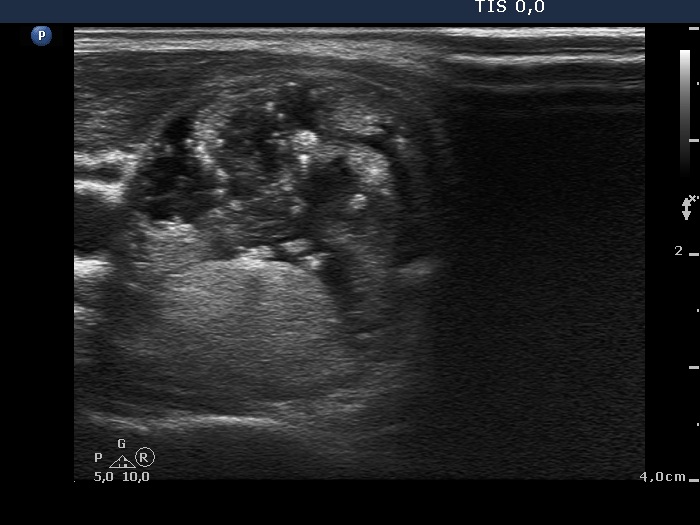

Intrathyroidal parathyroid adenoma (histological diagnosis) - case 1399 |

Papillary carcinoma (histological diagnosis) - case conp 031 |

There are a few hyperechogenic granules within the small parathyroid lesion and we can see two much thinner lines, as well. These figures might be either punctate echogenic foci or non-specific granules. The papillary carcinoma contains punctate echogenic foci. The main differences between the appearance of the cases are the shape and borders: regular and sharp in the left benign, while irregular, blurred in the right malignant focus.